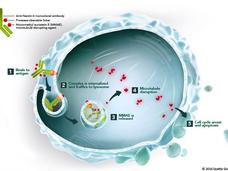

Enfortumab Vedotin Approved for Recurrent Bladder Cancer

Enfortumab vedotin-ejfv (Padcev) has been approved for people with advanced bladder cancer. FDA granted the drug accelerated approval for cancers that have progressed despite previous treatments.